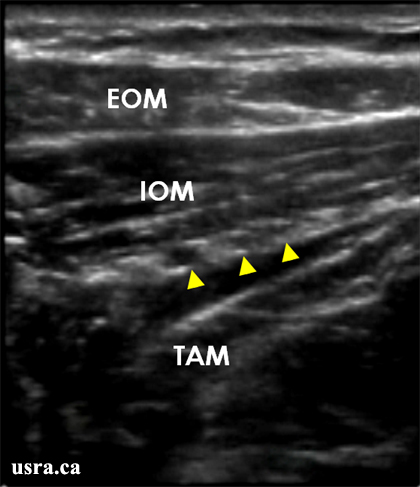

Regional anesthesia techniques for inguinal surgeries. Ultrasound guided ilioinguinal block. This nerve block is used most commonly to diagnose and treat the common entrapment neuropathy ilioinguinal neuralgia 2. Block of the iliohypogastric and ilioinguinal nerves results in anesthesia of the hypogastric region the inguinal crease the upper medial thigh the mons pubis part of the labia the root of the penis and the anterior part of the scrotum.

Ilioinguinal nerve block has shown great utility as a diagnostic prognostic and therapeutic maneuver in the evaluation and treatment of groin and genital pain thought to be mediated via the ilioinguinal nerve 1. We have used a supra inguinal approach to the fascia iliaca block under ultrasound guidance over a period of three years in over 150 patients. Ultrasound guided fascia iliaca block in the infra inguinal area has been described previously 5 6. Blockade of the ii and ih nerves is indicated for analgesia following inguinal hernia repair because the nerves provide sensory innervation to the skin of the lower abdominal wall in addition to the upper hip and upper thigh.